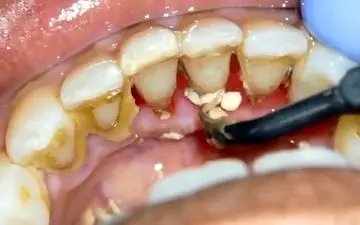

ایجاد جرم دندانی، مشکلی رایج ناشی از عدم رعایت صحیح بهداشت دهان و دندان است. دکتر مصطفی مژدهی فرد، دندانپزشک، بر اهمیت…

متخصص بیماریهای لثه دانشگاه علوم پزشکی شهیدبهشتی، گفت: جرمگیری برای سایر درمانهای دندانپزشکی بهعنوان درمان مادر…